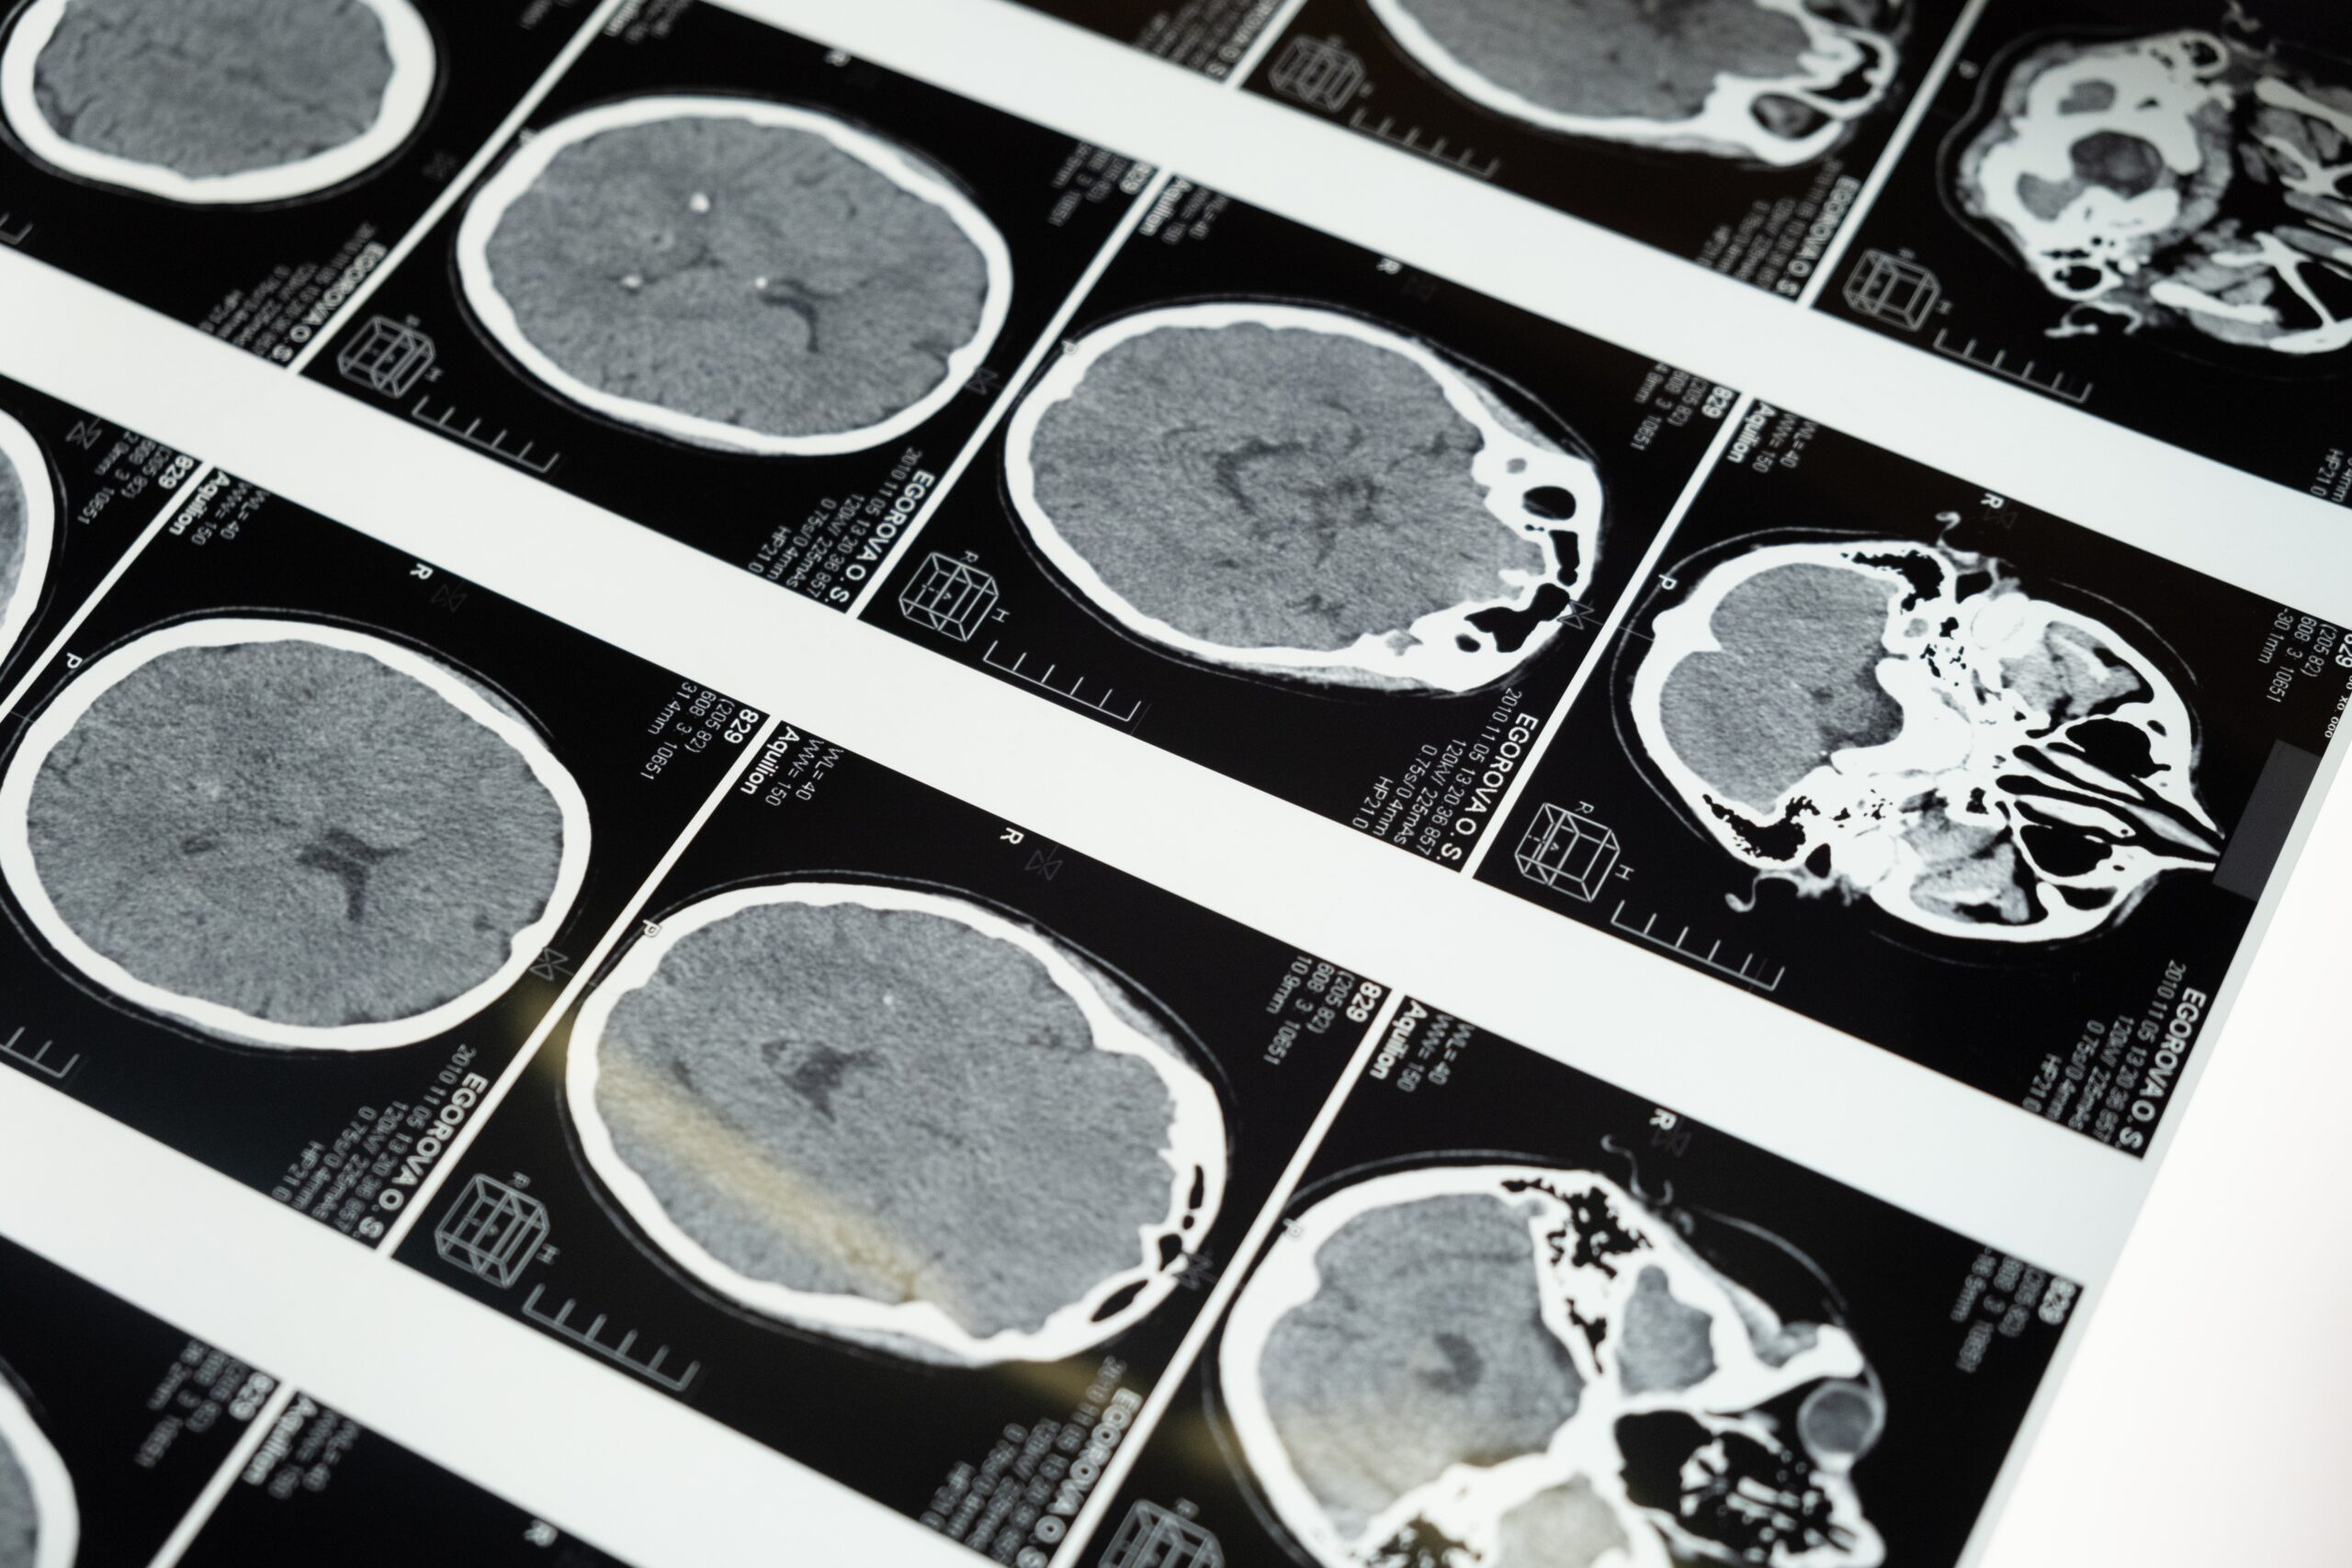

Εργαλείο τεχνητής νοημοσύνης αποκωδικοποιεί το γονιδίωμα του καρκίνου του εγκεφάλου κατά τη διάρκεια της χειρουργικής επέμβασης για την αφαίρεσή του. Η δημιουργία του προφίλ του όγκου σε πραγματικό χρόνο μπορεί να καθοδηγήσει τις χειρουργικές θεραπευτικές αποφάσεις. Η έρευνα δημοσιεύτηκε στο περιοδικό Med.

Η επιστημονική ομάδα, με επικεφαλής την Ιατρική Σχολή του Χάρβαρντ, σχεδίασε ένα εργαλείο τεχνητής νοημοσύνης που μπορεί να αποκωδικοποιήσει γρήγορα κατά τη διάρκεια χειρουργικής επέμβασης το DNA ενός όγκου στον εγκέφαλο, προκειμένου να προσδιορίσει τη μοριακή του ταυτότητα. Οι πληροφορίες αυτές είναι κρίσιμες, καθώς με την τρέχουσα προσέγγιση μπορεί να χρειαστούν από μερικές ημέρες έως και μερικές εβδομάδες για να συλλεχθούν.